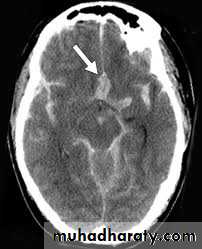

Non contrast high resolution CT scan which can demonstrate the amount of blood in the cisterns and fissure, ventricular size, associated intracranial hemorrhage, infarction and predict the location of aneurysm.

Pial enhancement on CT scan